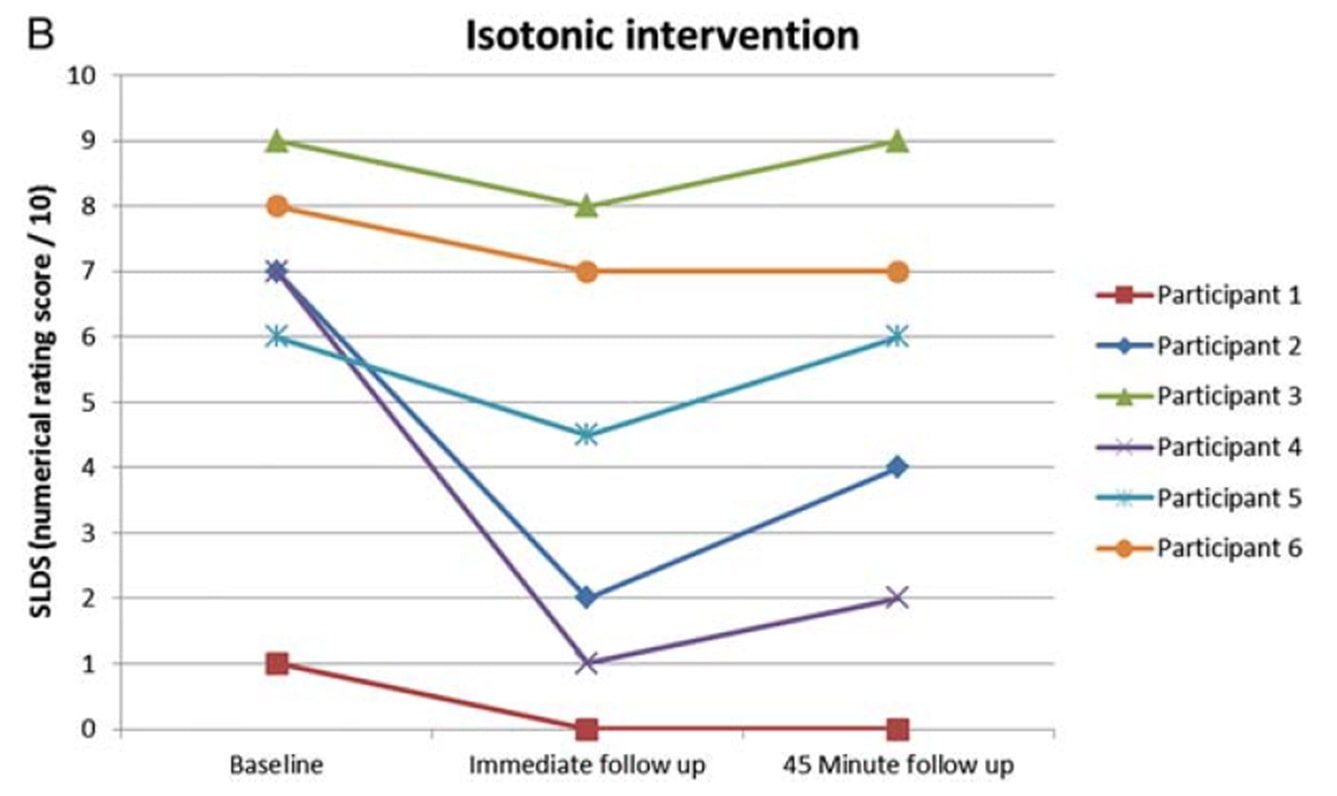

Rio et al. (2015) haben mit einer Cross-Over-Studie an 6 Volleyballspielern mit Patellaspitzentendinopathie einen neuen Trend ausgelöst. Die Ergebnisse waren erstaunlich: Bei allen Spielern ging der Schmerz sofort von durchschnittlich 7/10 auf der NRS auf 0 zurück, und nur einer der sechs Spieler meldete nach den isometrischen Kontraktionen mindestens 45 Minuten lang einen Restschmerz von 1. Das Protokoll, das sie verwendeten, bestand aus 5 Sätzen mit 45 Sekunden Kontraktion an einer Beinstreckmaschine und einer Anstrengung von 70 % der maximalen freiwilligen Anstrengung. Sie fanden auch heraus, dass isometrische Übungen die kortikale Hemmung verringern und die Kraft um 19 % steigern konnten. Sie verglichen die isometrische Intervention mit einer isotonischen Intervention, und die in der isometrischen Gruppe beobachteten Effekte konnten in der isotonischen Gruppe nicht erreicht werden:

Dieselben Autoren führten zwei Jahre später eine Folgestudie mit springenden Athleten durch (Rio et al. 2017), in der sie ein isometrisches Programm und ein isotonisches Programm miteinander verglichen. In dieser Studie waren die Ergebnisse bei beiden Gruppen etwas uneinheitlicher, wobei die isometrische Gruppe eine stärkere unmittelbare Schmerzlinderung verzeichnete: